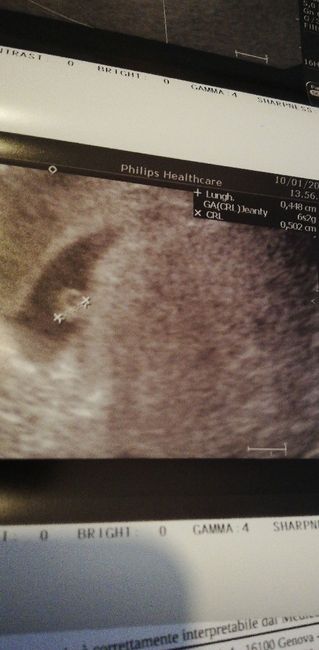

Mamme Settembre 2020❤️

Da Lu Do , Il 10 Gennaio 2020 alle 16:20

Apro il topic di settembre 2020 sperando che saremo in tantissime! Auguri a tutte!!